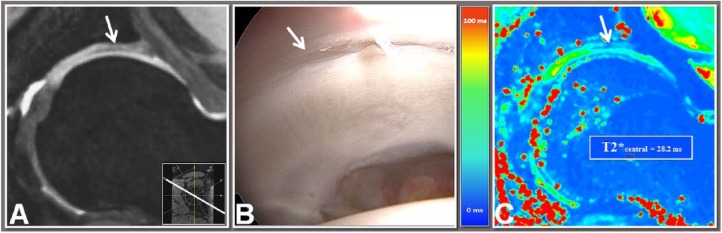

Figure 2.

A 10 o’clock double-echo steady-state (DESS) reformat (A), an intraoperative view (B) of the corresponding region (arrows), and a 10 o’clock T2* map reformat (C) of a 15-year-old male patient with anterosuperior femoroacetabular impingement (FAI). T2* values were obtained using a region of interest (ROI) analysis in central and peripheral acetabular cartilage. The corresponding DESS reformat served as a guide to ensure ROI placement within cartilage boundaries. Note no cartilage degeneration was observed in this region, either with DESS MRI, intraoperative correlation or T2* relaxometry.